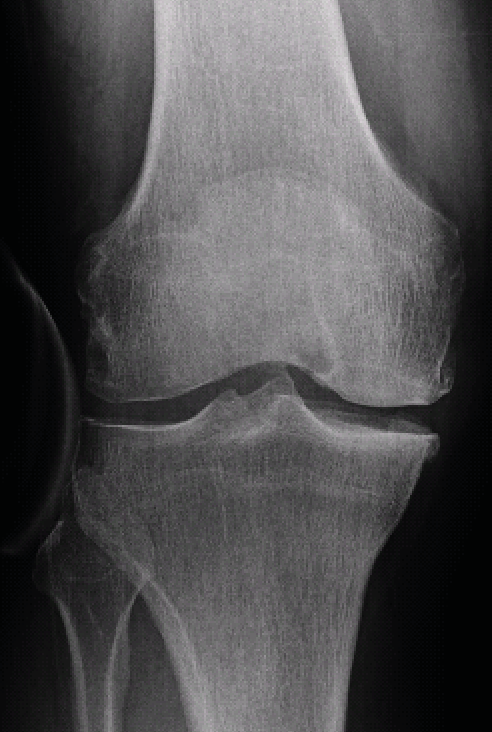

Radiographic analysis requires a weight-bearing full leg and lateral knee joint x-ray and a standard axial image of the patella. In addition, the extent of the narrowing of the joint space in the affected joint compartment should be assessed with a Rosenberg view (p.a. radiograph with weight-bearing and 45 degrees of flexion) or stress x-rays with varus/valgus stress. Since large numbers of unicondylar knee replacements are performed in our hospital, stress radiographs are standard for any unicompartmental OA requiring surgical treatment. The extent of the joint collapse and the stability of the joint can be diagnosed by these radiographs (Fig. 6, 7).